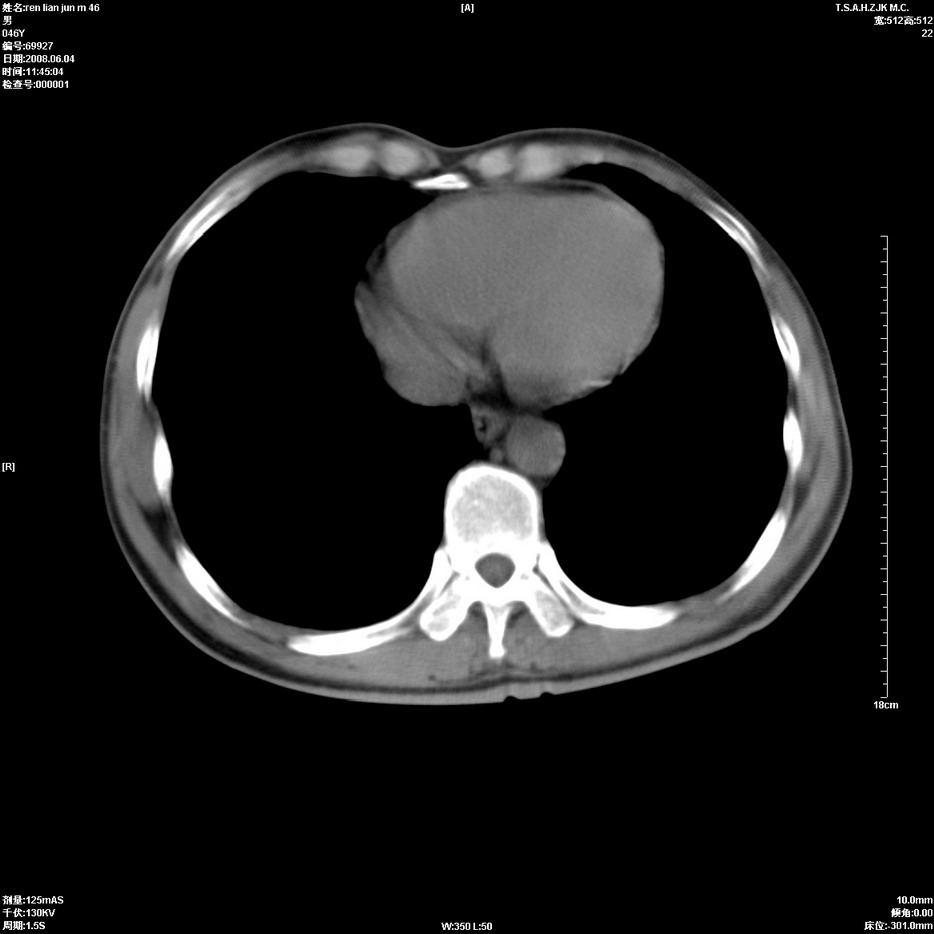

以下是引用qiu999在2008-6-5 17:14:00的发言:[br]考虑右肺中心型肺癌.颅内应做增强检查.

以下是引用形影不离在2008-6-5 19:18:00的发言:[br]右肺中心型肺癌并纵隔及左侧腋窝淋巴结转移,颅内应做增强检查。

以下是引用杀毒软件在2008-6-5 18:33:00的发言:[br]支持考虑右肺中心型肺癌,颅内病变是不是转移,不好说